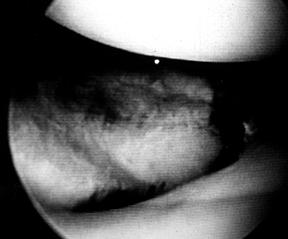

![]() |

|

Figure 23.6.

Arthroscopic view of a split fracture of the lateral tibial plateau. One can obtain good visualization of the articular surface, femoral condyles, and meniscus. |